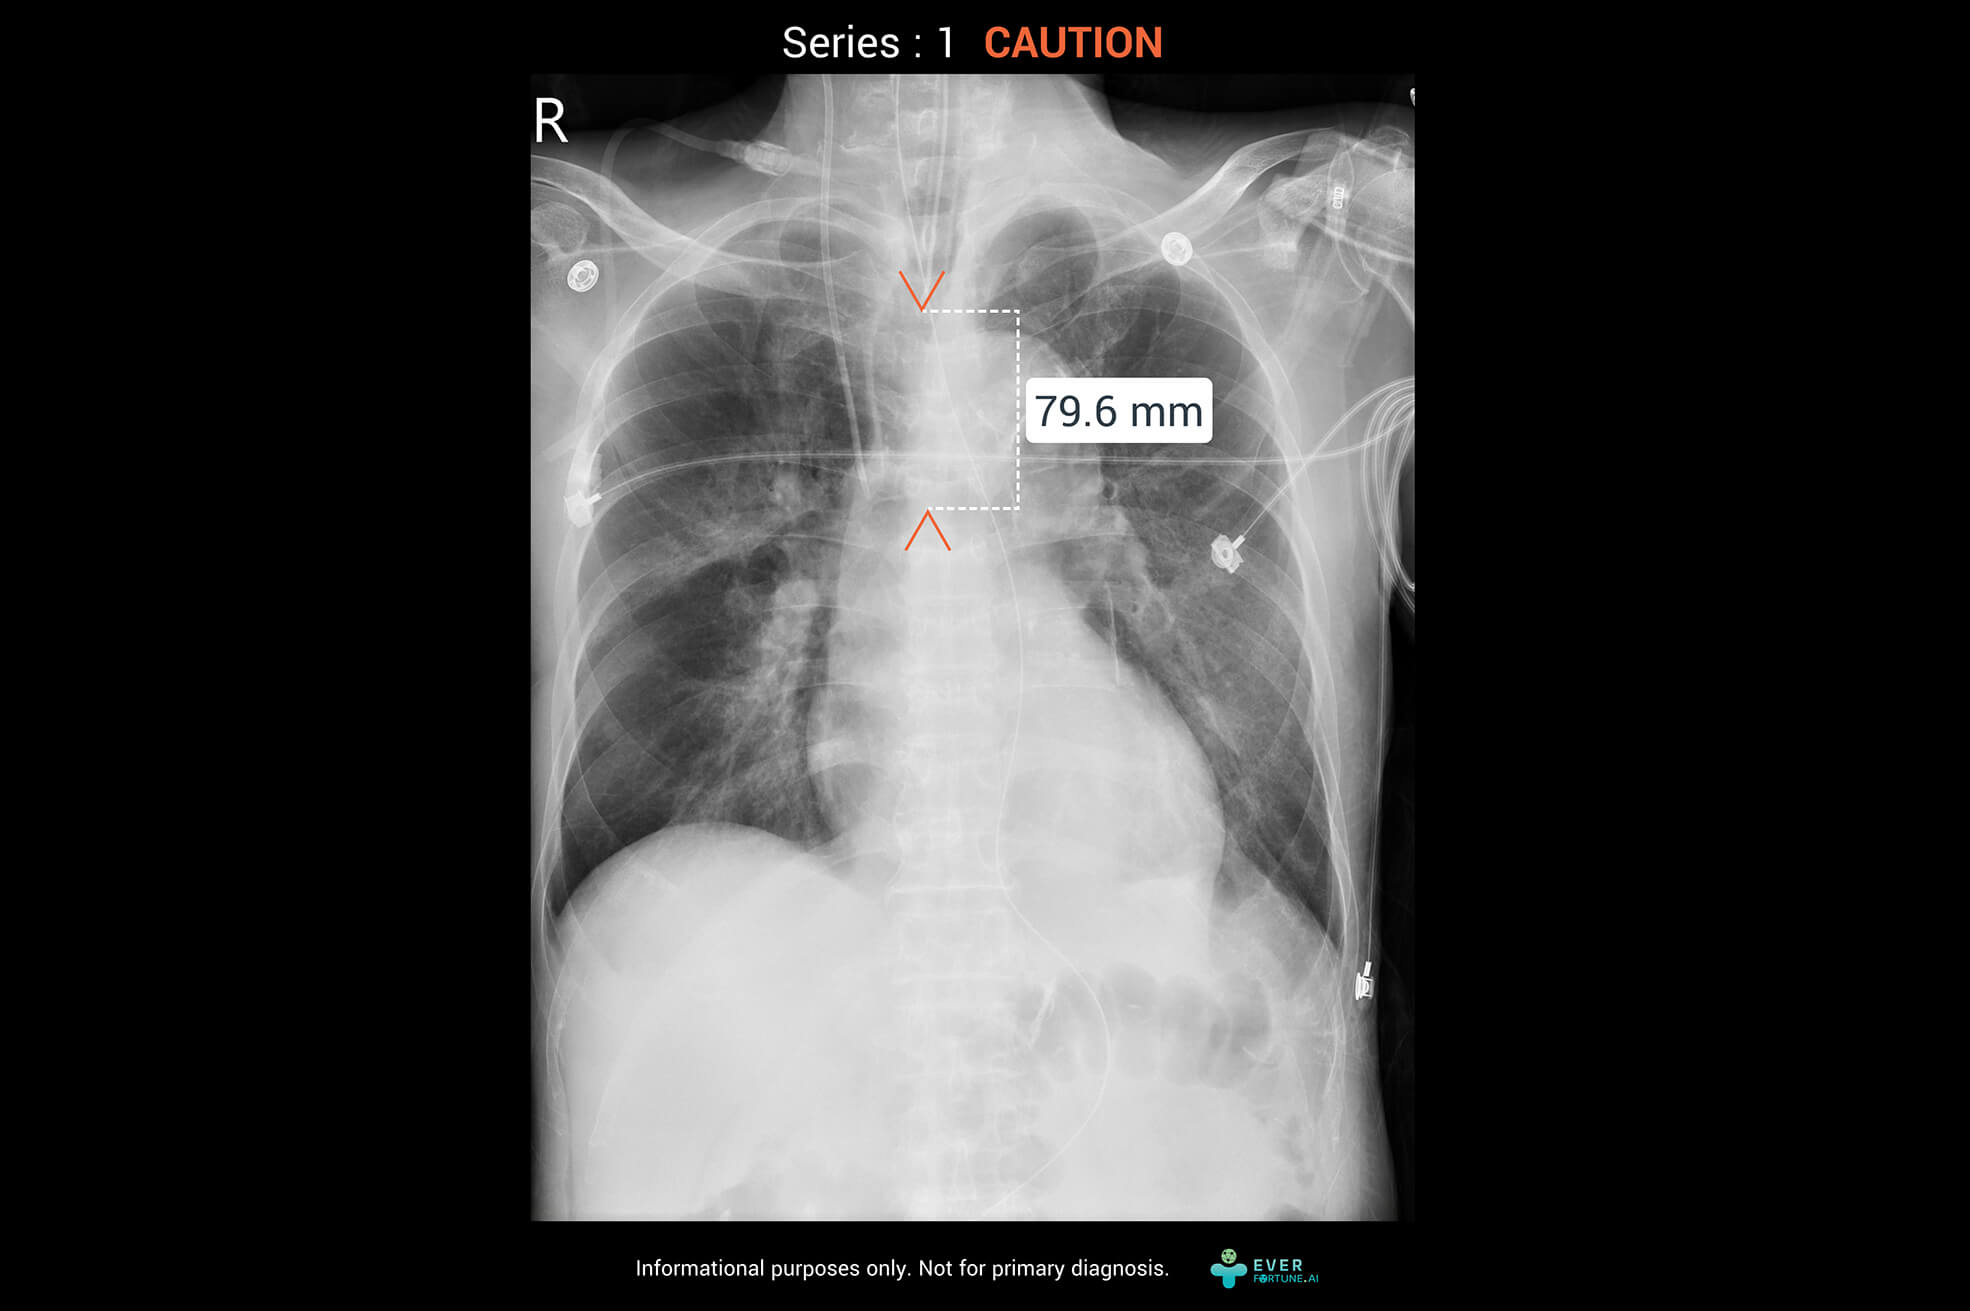

Our AI assistant for chest X-ray interpretation simultaneously assesses pneumothorax, pleural effusion, cardiothoracic ratio, and endotracheal tube depth. It provides key images seamlessly integrated with PACS for fast, highly accurate analysis results.

Identify 15 abnormal finding in chest X-ray images with heart, lungs and bones. The system as a pre-read assistance enable a quick interpretation and faster decisions